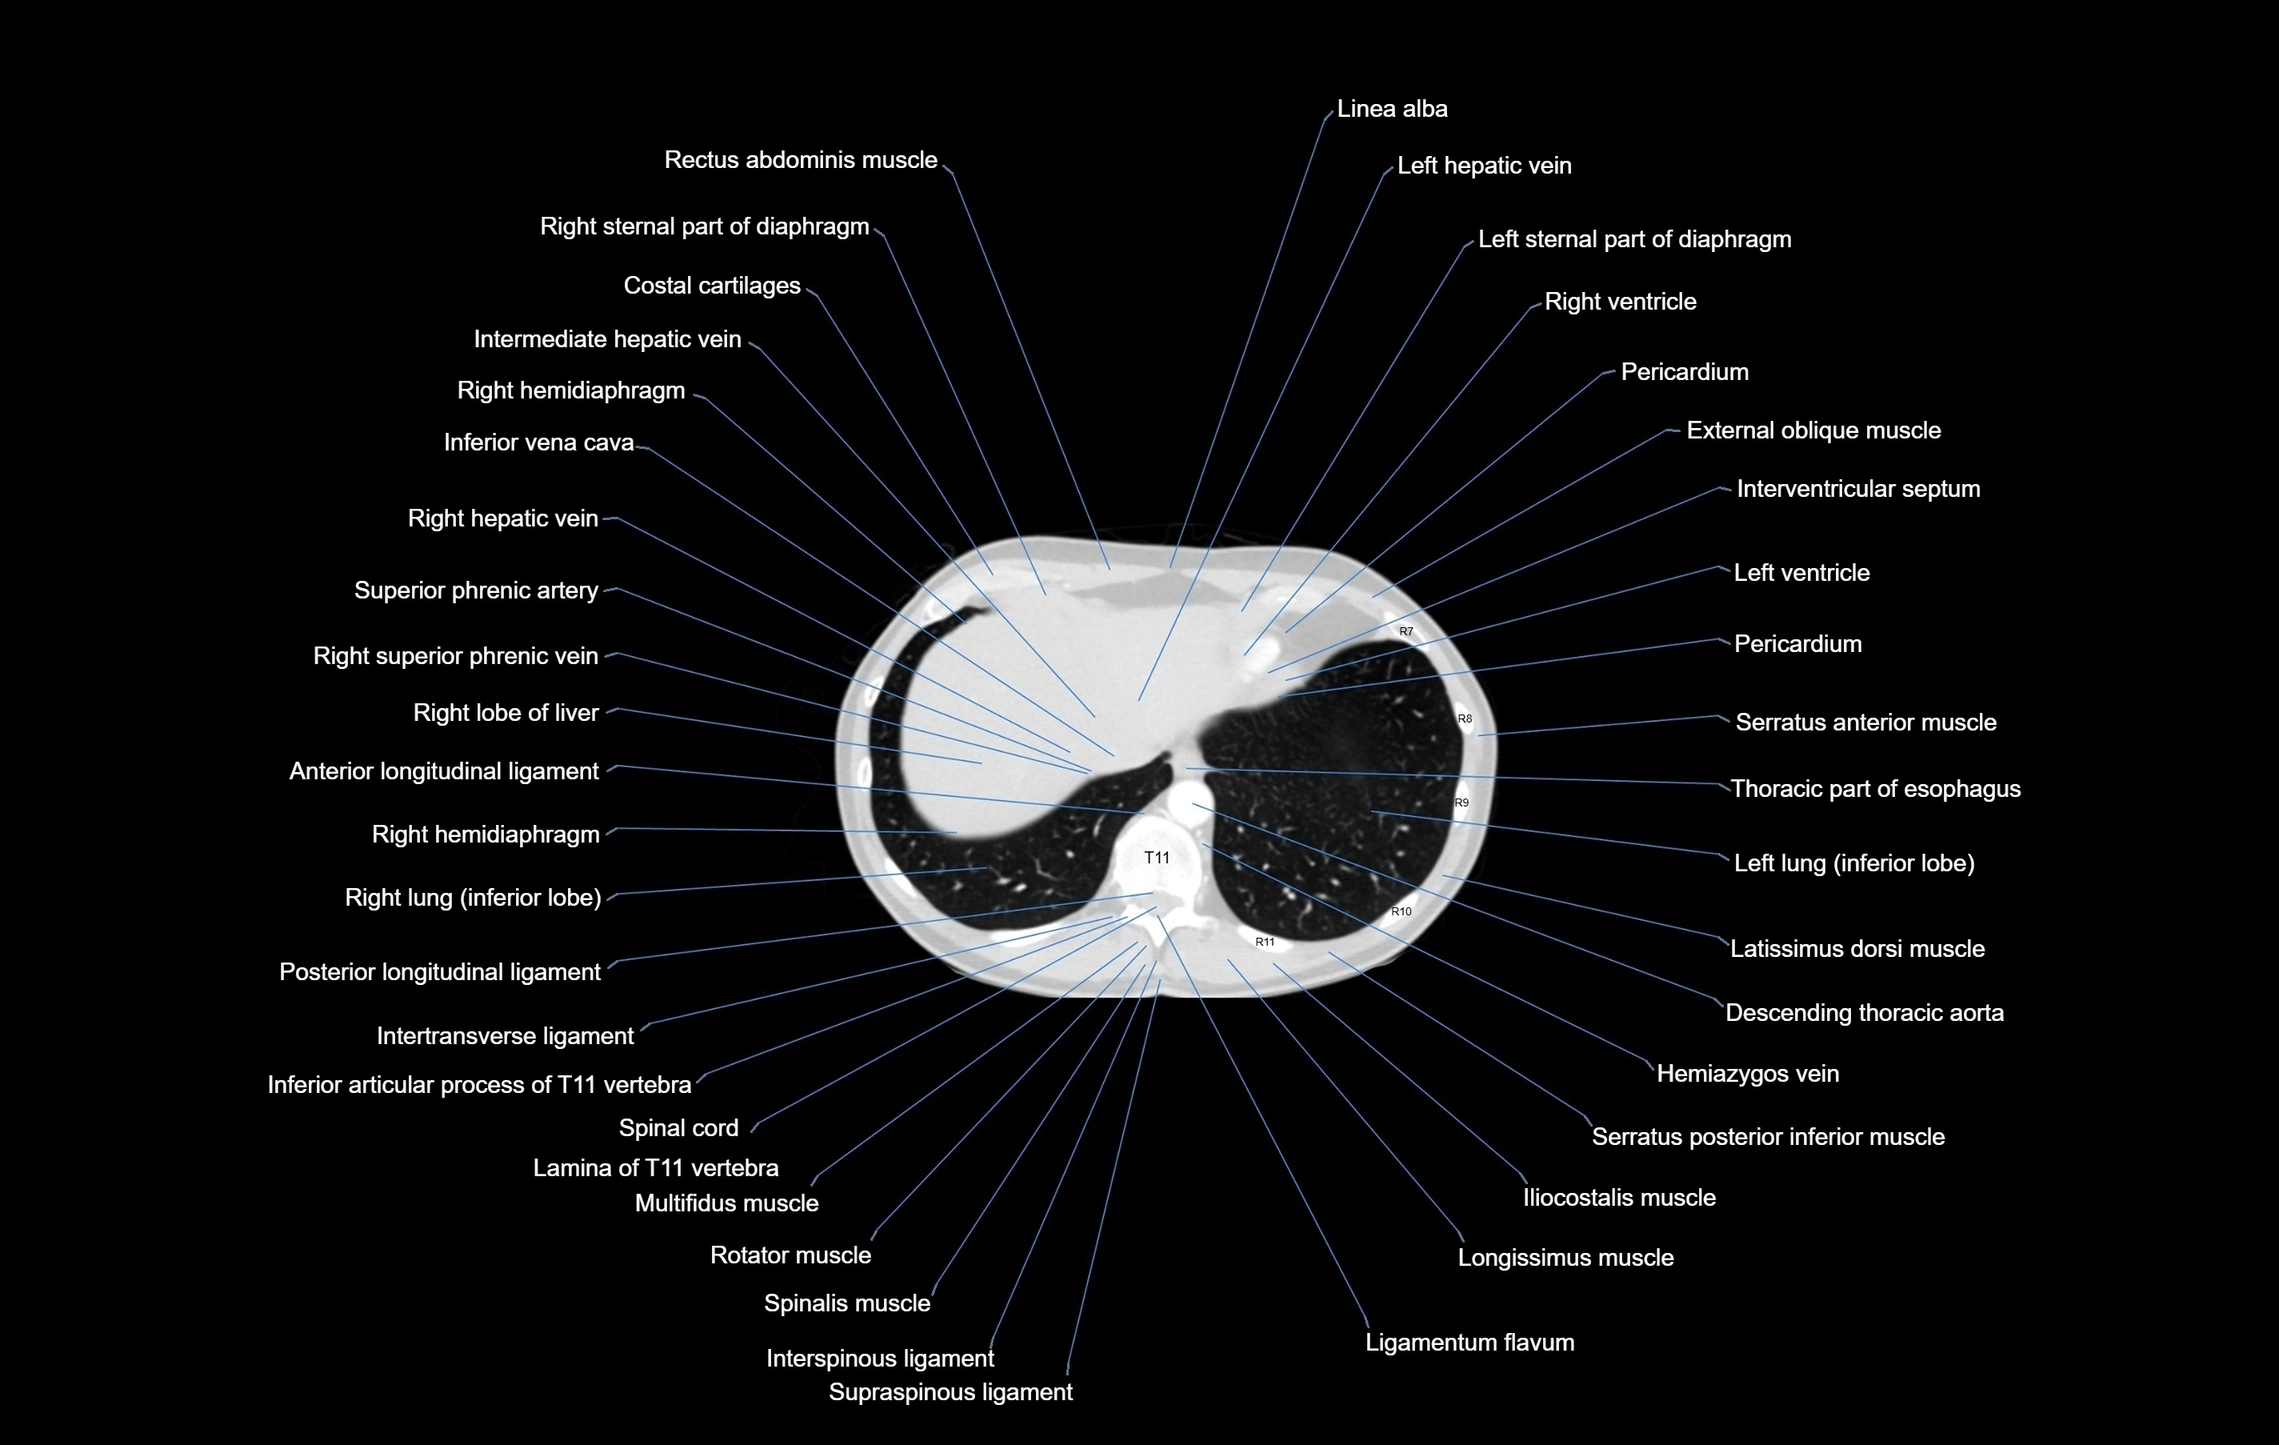

CT images